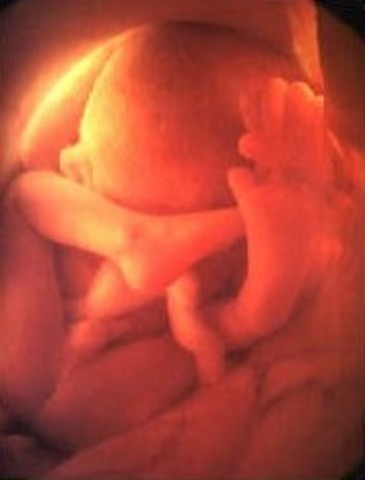

• Week Eight: Starts to practice moving

Week Eight: Starts to practice moving

The legs and arms are growing and the elbow and toes are visible.The feet and hand buds appear.

• Week 9: Fingers and Toes form

Week 9: Fingers and Toes form

The fingers and toes are vetu define. The bones atart to form.

• Week Ten: Embryo is now a Fetus

Week Ten: Embryo is now a Fetus

The developing organism is called a fetus.It is the size of a small strawberry.